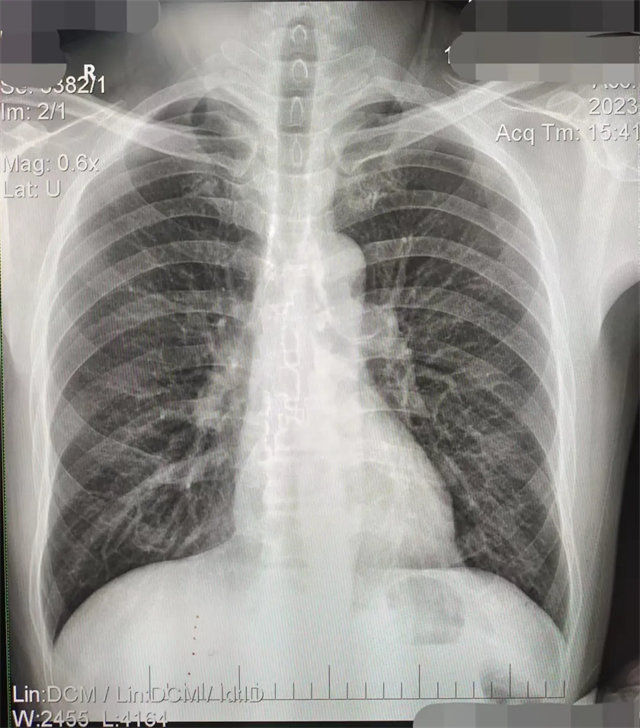

缺陷:雙側胸鎖關節不對稱,且有手機顯影。

解決:去除手機后,使患者左側緊貼成像件曝光。